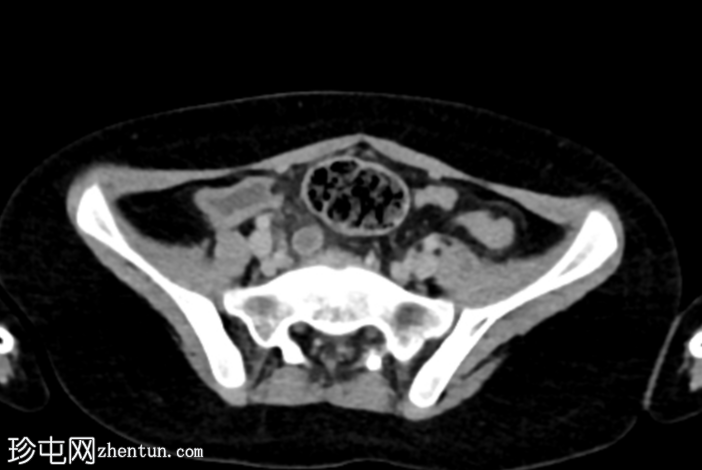

轴位增强扫描(门静脉期)

阑尾充血膨胀,直径10 mm,轻度壁增厚及强化,周围脂肪间隙模糊。

回盲部及阑尾开口轻度壁增厚,可能为炎症性增生(回结肠炎)。

右髂系膜淋巴结肿大。

该病例的影像学表现符合急性阑尾炎的典型特征,表现为阑尾充血膨胀(最大直径10 mm),轻度壁增厚及强化,周围脂肪间隙模糊。

本病例的其他发现包括右髂窝肠系膜淋巴结肿大(反应性增生)和回盲部肠壁增厚,这可能代表反应性肠壁增厚(继发于阑尾炎),但更可能在本病例中,是炎症/感染(回结肠炎)的早期阶段,最终扩散至阑尾开口,导致阑尾开口管腔狭窄,进而发展为急性真性阑尾炎——本病例中未见阑尾粪石阻塞阑尾开口。